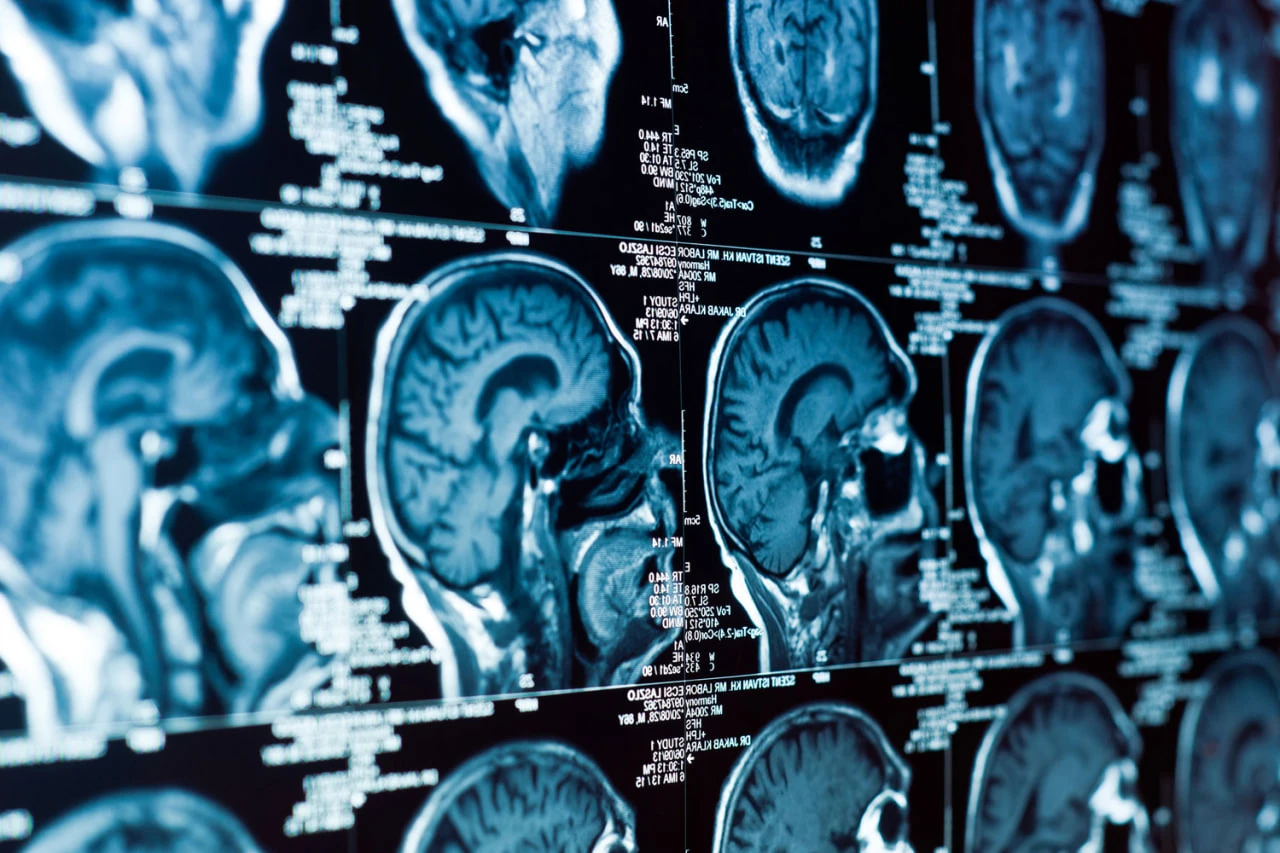

Alzheimer's disease disrupts the circadian rhythms of brain cells responsible for clearing toxic plaques. Scientists from the University of Washington School of Medicine came to this conclusion. The study was published in the journal Nature Neuroscience (NatNeuro).

The team, led by neuroscientist Eric Muzik, found that amyloid plaques, a key feature of the disease, disrupt the function of hundreds of genes that regulate the circadian rhythms of microglia and astrocytes. These cells act as "cleaners" of the brain. microglia clear the tissue of toxins and dead cells, while astrocytes maintain neuronal function.

In experiments on mice, the researchers showed that when amyloid accumulates, the normal rhythms of gene activity in these cells are disrupted, turning the orderly system into a chaotic one. As a result, the synchronous activity of the mechanisms responsible for amyloid clearance is disrupted. Furthermore, amyloid creates "new rhythms" in hundreds of other genes associated with inflammation.